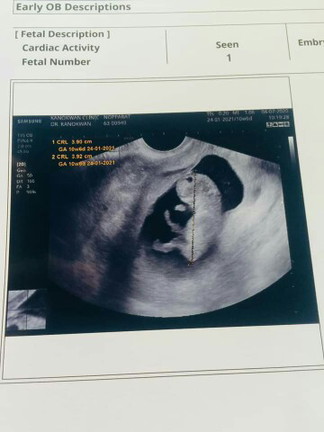

10w6d

น้องตัวยาวไปมั้ยค่ะ 10+6 ยาว3.92cm.